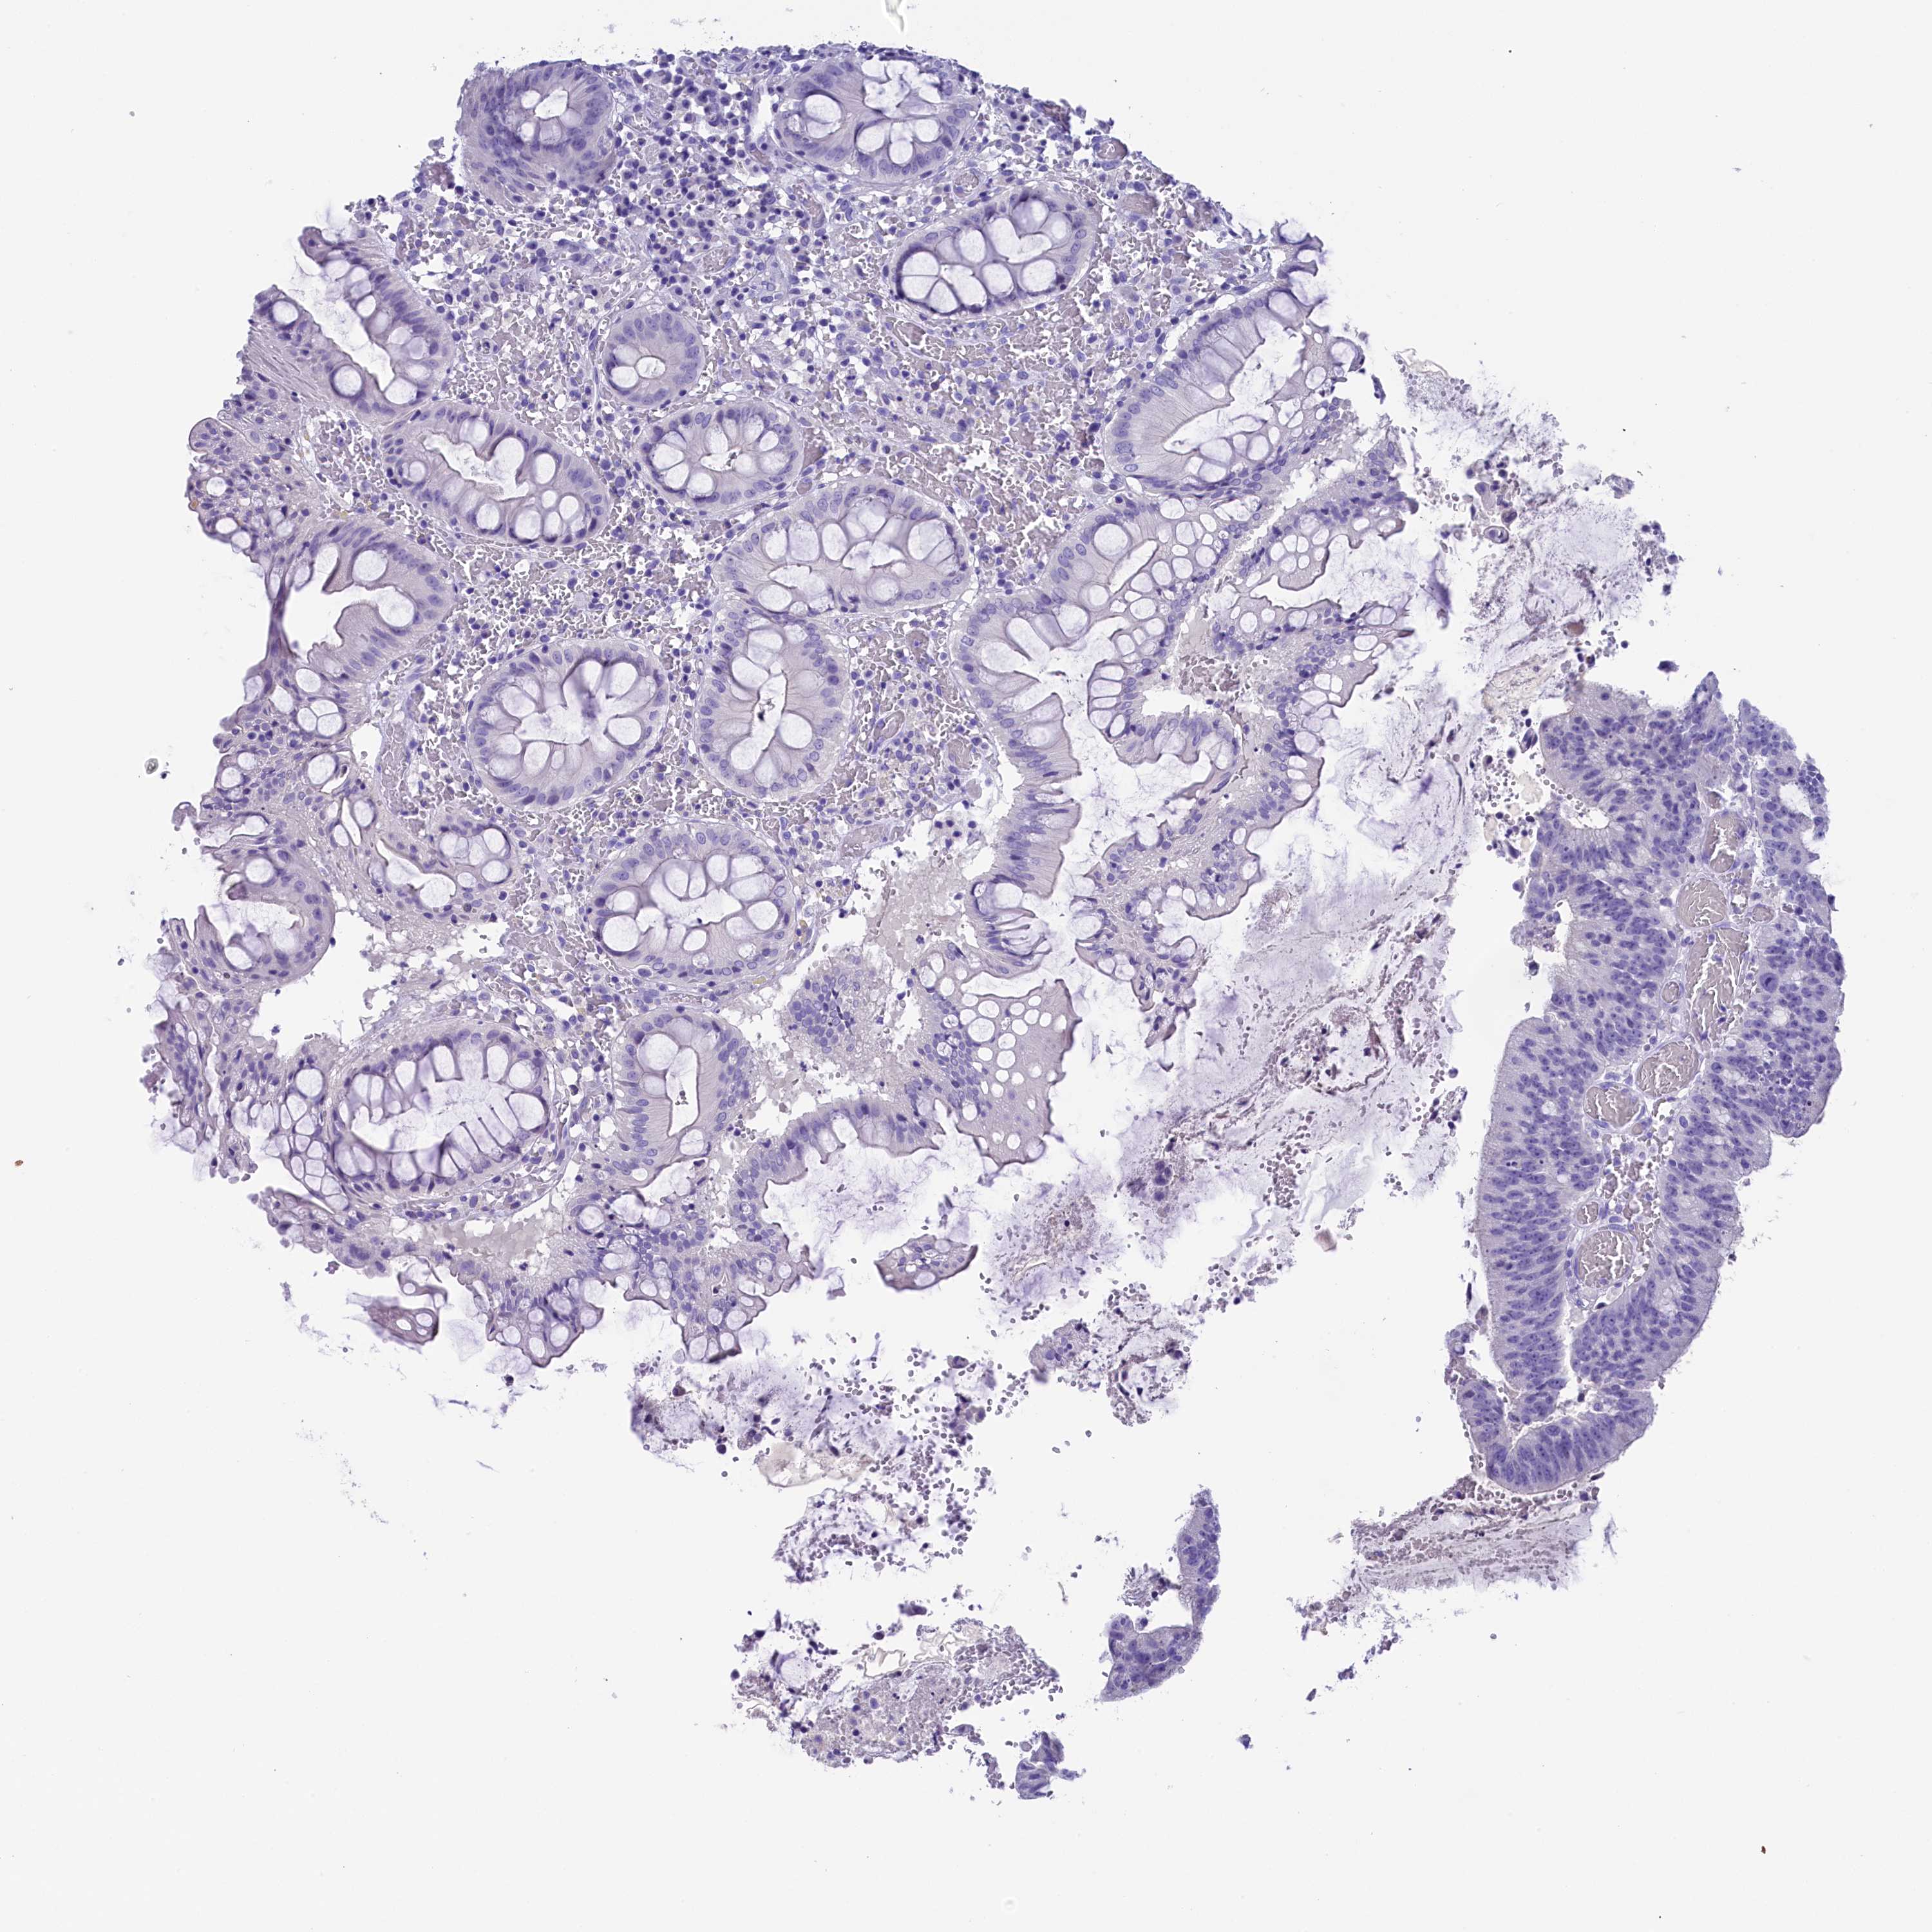

CANCER COLORECTAL CANCER Show tissue menu

Colorectal cancer

Human cancer

Colon adenocarcinoma